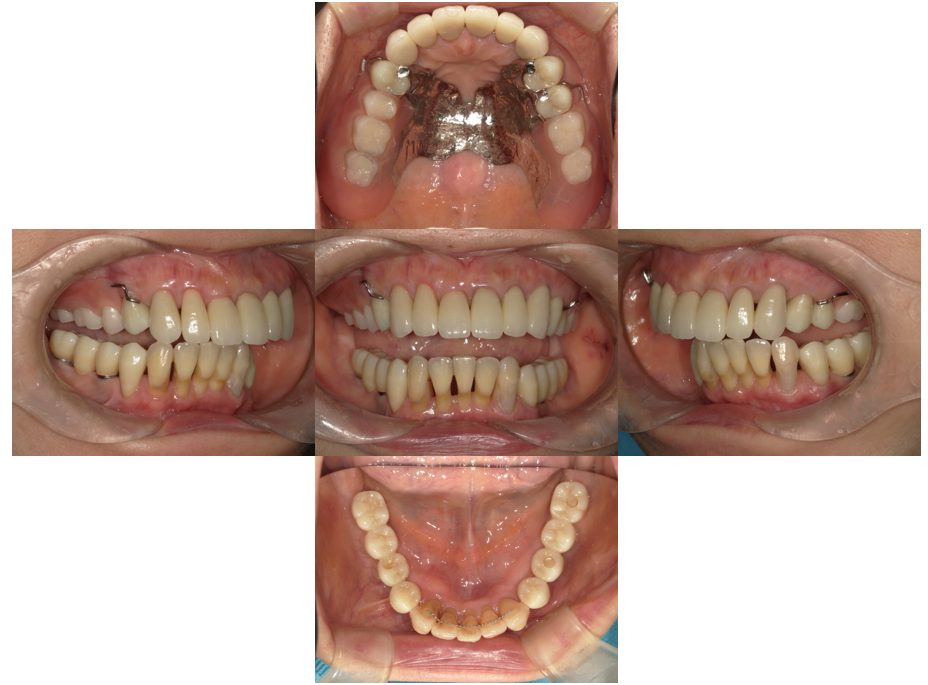

矯正治療・インプラント治療・セラミック治療の症例紹介(三隅歯科クリニック)

三隅 賢祐(三隅歯科クリニック)

症例詳細

| 主訴 | 30代女性 顎関節が痛い。見た目も気になる |

| 治療内容 | 矯正治療を行いました。 |

| 治療費 | 1,700,000円(税込み) |

| 治療期間 | 3年(矯正治療期間 2年半) |

| 治療回数 | 40回 |

| 想定されたリスク | 術前に精密な診査診断とシミュレーションを行い、インプラントを適正なポジションに埋入しておかないと、インプラント自体が矯正治療の邪魔になるリスクがあった。 |